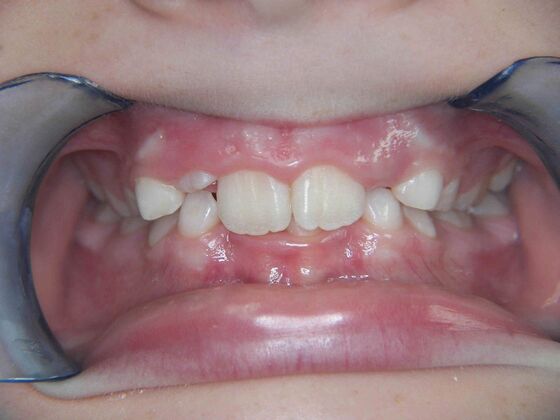

Patient is 9 years old and presents with 100% overbite and blocked out upper and lower lateral incisors. Both upper central incisors are palatally inclined causing a lack of space available for most anterior teeth. Advised her parents that she needs Phase I Interceptive Orthodontic treatment to provide room for all upper and lower front teeth. Phase I treatment was begun and finished, then began Phase II treatment shortly thereafter to finalize case. Removable retainer were fabricated for retention.